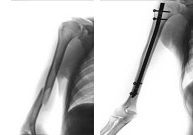

El hueso de la región del brazo es la porción media del húmero. Las fracturas a este nivel son poco frecuentes (5%) y obedecen a un impacto de alta energía, ya que, en esta región, el hueso es de tipo cortical y por lo tanto muy duro. Los deportes de contacto como las artes marciales, así como, deportes que puedan producir caídas violentas (automovilismo, motociclismo, ciclismo, barranquismo, parapente) predisponen asufrir este tipo de fracturas. Su tratamiento generalmente suele ser no quirúrgico pero en algunas ocasiones la estabilización requiere de una mínima intervención para la introducción de un tutor intraóseo de forma que el paciente pueda reincorporarse a su actividad habitual lo antes posible.